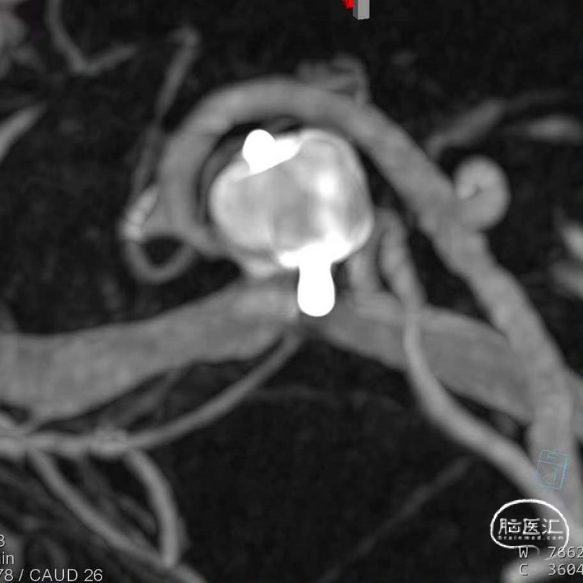

基底动脉末端动脉瘤不显影,动脉瘤完全闭塞,WEB™完全栓塞。

大脑中动脉瘤充分栓塞,瘤颈残留,WEB™充分栓塞。WEB™被压缩且位置偏转,分支血管有影响。